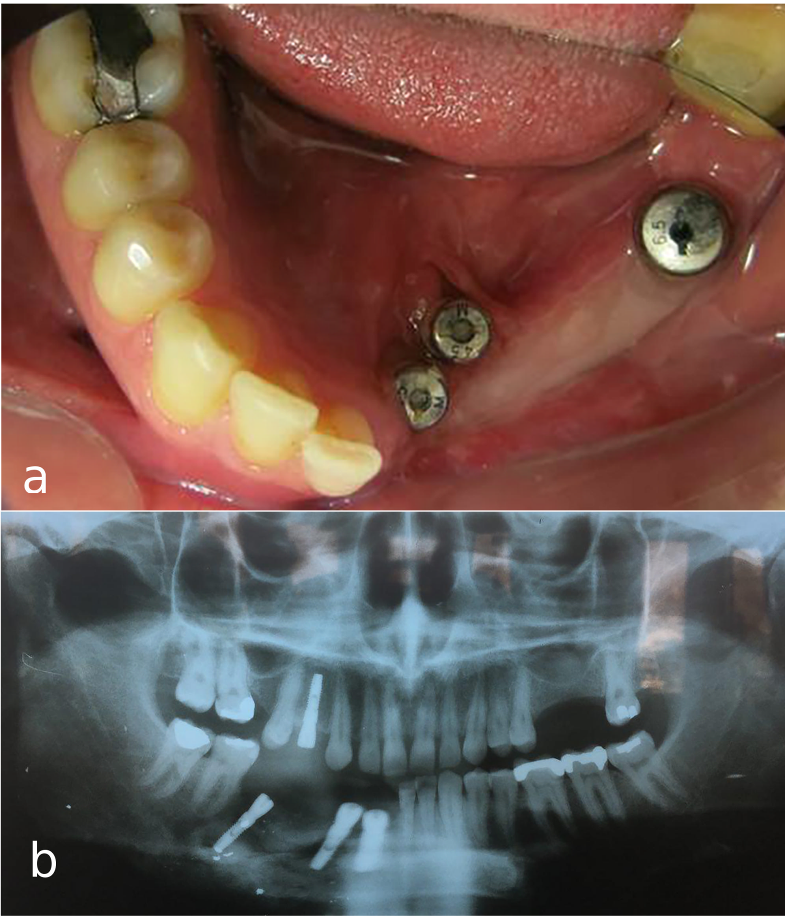

A 30-year-old partially edentulous patient was referred to the Implant Department of Tehran University, School of Dentistry, for prosthetic reconstruction (Figure 1, a and b). The patient had lost 6 teeth due to the trauma of a gunshot. Since the accident had occurred several years prevoiusly and the patient had undergone cosmetic plastic surgery, only a skin scar remained in his lower face. Three implants (Implantium, Dentium, Seoul, South Korea) were placed on the left side of the mandible (Figure 2, a and b). Regarding the increased interocclusal space and improper implant alignment, it was decided to use hybrid screw-retained and cement-retained implant (Toronto) prosthesis.

a) Occlusal view of mandibular arch with three implants. b) Panoramic view of implants placed in defective bone in the left mandible.